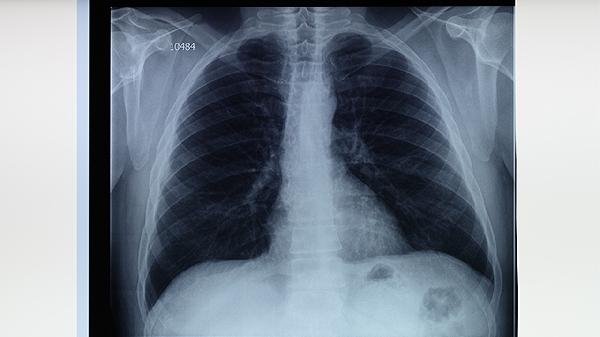

中醫(yī)治療肺結核需辨證施治,不同階段采用相應方藥。治療期間應保持情緒穩(wěn)定,避免勞累,居住環(huán)境需通風但避風寒。飲食宜清淡營養(yǎng),忌煙酒及辛辣刺激。需定期復查胸部影像學,若出現(xiàn)大咯血、呼吸困難等急癥應立即就醫(yī)。中西醫(yī)結合治療可提高療效,抗結核西藥不可擅自停用。